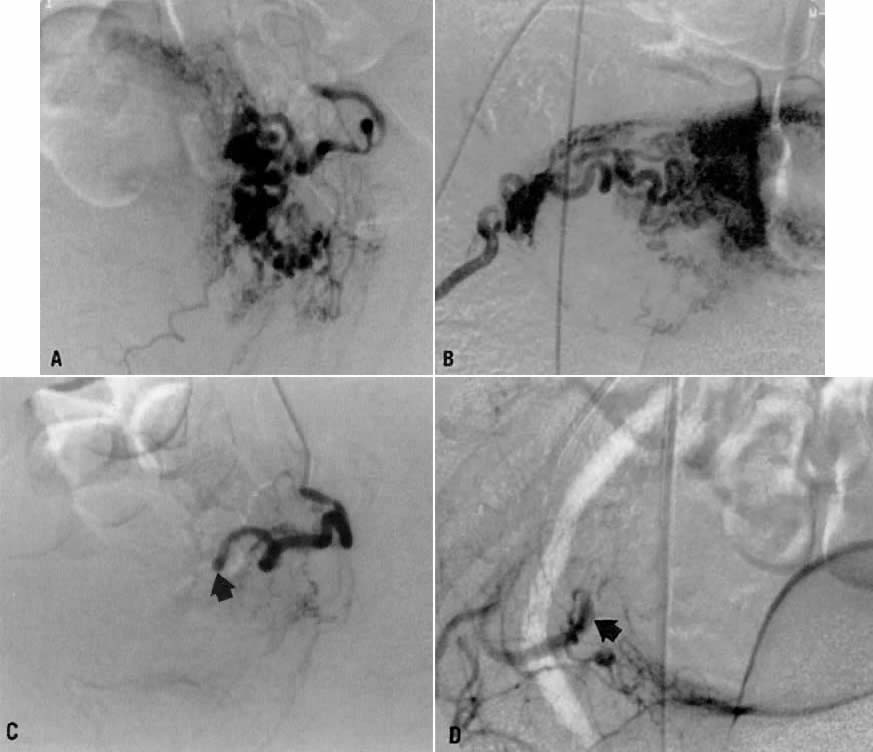

Case 6.

This 16-year-old patient (gravida 3, para 0) had experienced three spontaneous first-trimester abortions, all with significant hemorrhage. After the third abortion, hysteroscopy demonstrated multiple enlarged pulsatile uterine arteries in the uterine fundus; a clinical diagnosis of uterine arteriovenous malformation was made. Figure 23A is an anteroposterior view of the pelvis, demonstrating an enlarged right uterine artery supplying a hypervascular mass. Note the normal left uterine artery. Figure 23B shows the late arterial phase, in which there is early venous drainage.

Fig. 23. Case 6. Congenital uterine arteriovenous malformation. A. Anteroposterior pelvic arteriogram shows enlarged right uterine artery supplying a hypervascular mass ( asterisk ), and normal left uterine artery ( arrow ). B. Late arterial phase showing early venous drainage ( arrows ). C. Superselective right uterine arteriogram shows tortuous feeding arteries. D. Right common iliac artery injection showing no filling of arteriovenous malformation after embolization.(Vogelzang RL, Nemcek AA, Skirtic Z et al: Uterine arteriovenous malformations: Primary treatment with therapeutic embolization. J Vasc Interv Radiol 2:517, 1991)

Pelvic embolization was requested. Figure 23C shows subselective right uterine arteriography with tortuous dilated vessels supplying the mass. The malformation was embolized with polyvinyl foam particles (300 to 500 μm) and surgical gelatin pledgets. Complete occlusion of the right uterine artery was achieved. Because of the hypervascular nature of the mass, the left uterine artery also was embolized with polyvinyl alcohol particles. Figure 23D shows a right common iliac artery injection with obliteration of the arteriovenous malformation after embolization. Six months after embolization, the patient became pregnant again and had an uneventful first trimester; however, because of her persistent and overwhelming concerns about the possibility of bleeding, she insisted on and underwent an elective hysterectomy for termination of pregnancy. Pathologic examination of the uterus showed a thrombosed arteriovenous malformation without evidence of new vessels: Clearly, the embolization had been completely successful in obliterating the malformation. Unfortunately, the patient did not benefit from the therapy.